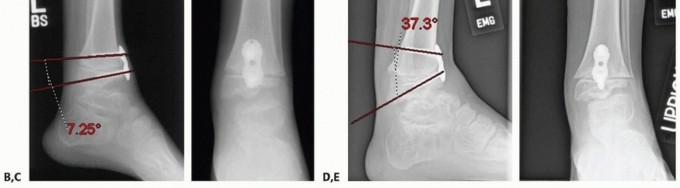

- FIG 5 • A. An 8-year-old boy with 20 degrees residual equinus and talus dysmorphology after revision posterior medial release. B,C. Anterior distal tibia guided growth was performed after a CT scan ensured appropriate sizing of the epiphysis. In this procedure, a modular implant is placed by putting a guide pin into the distal tibia epiphysis and then a cannulated screw is placed. D,E. Two years postoperatively, the patient now has 10 degrees of ankle dorsiflexion. (Courtesy of UW Pediatric Orthopaedics.)